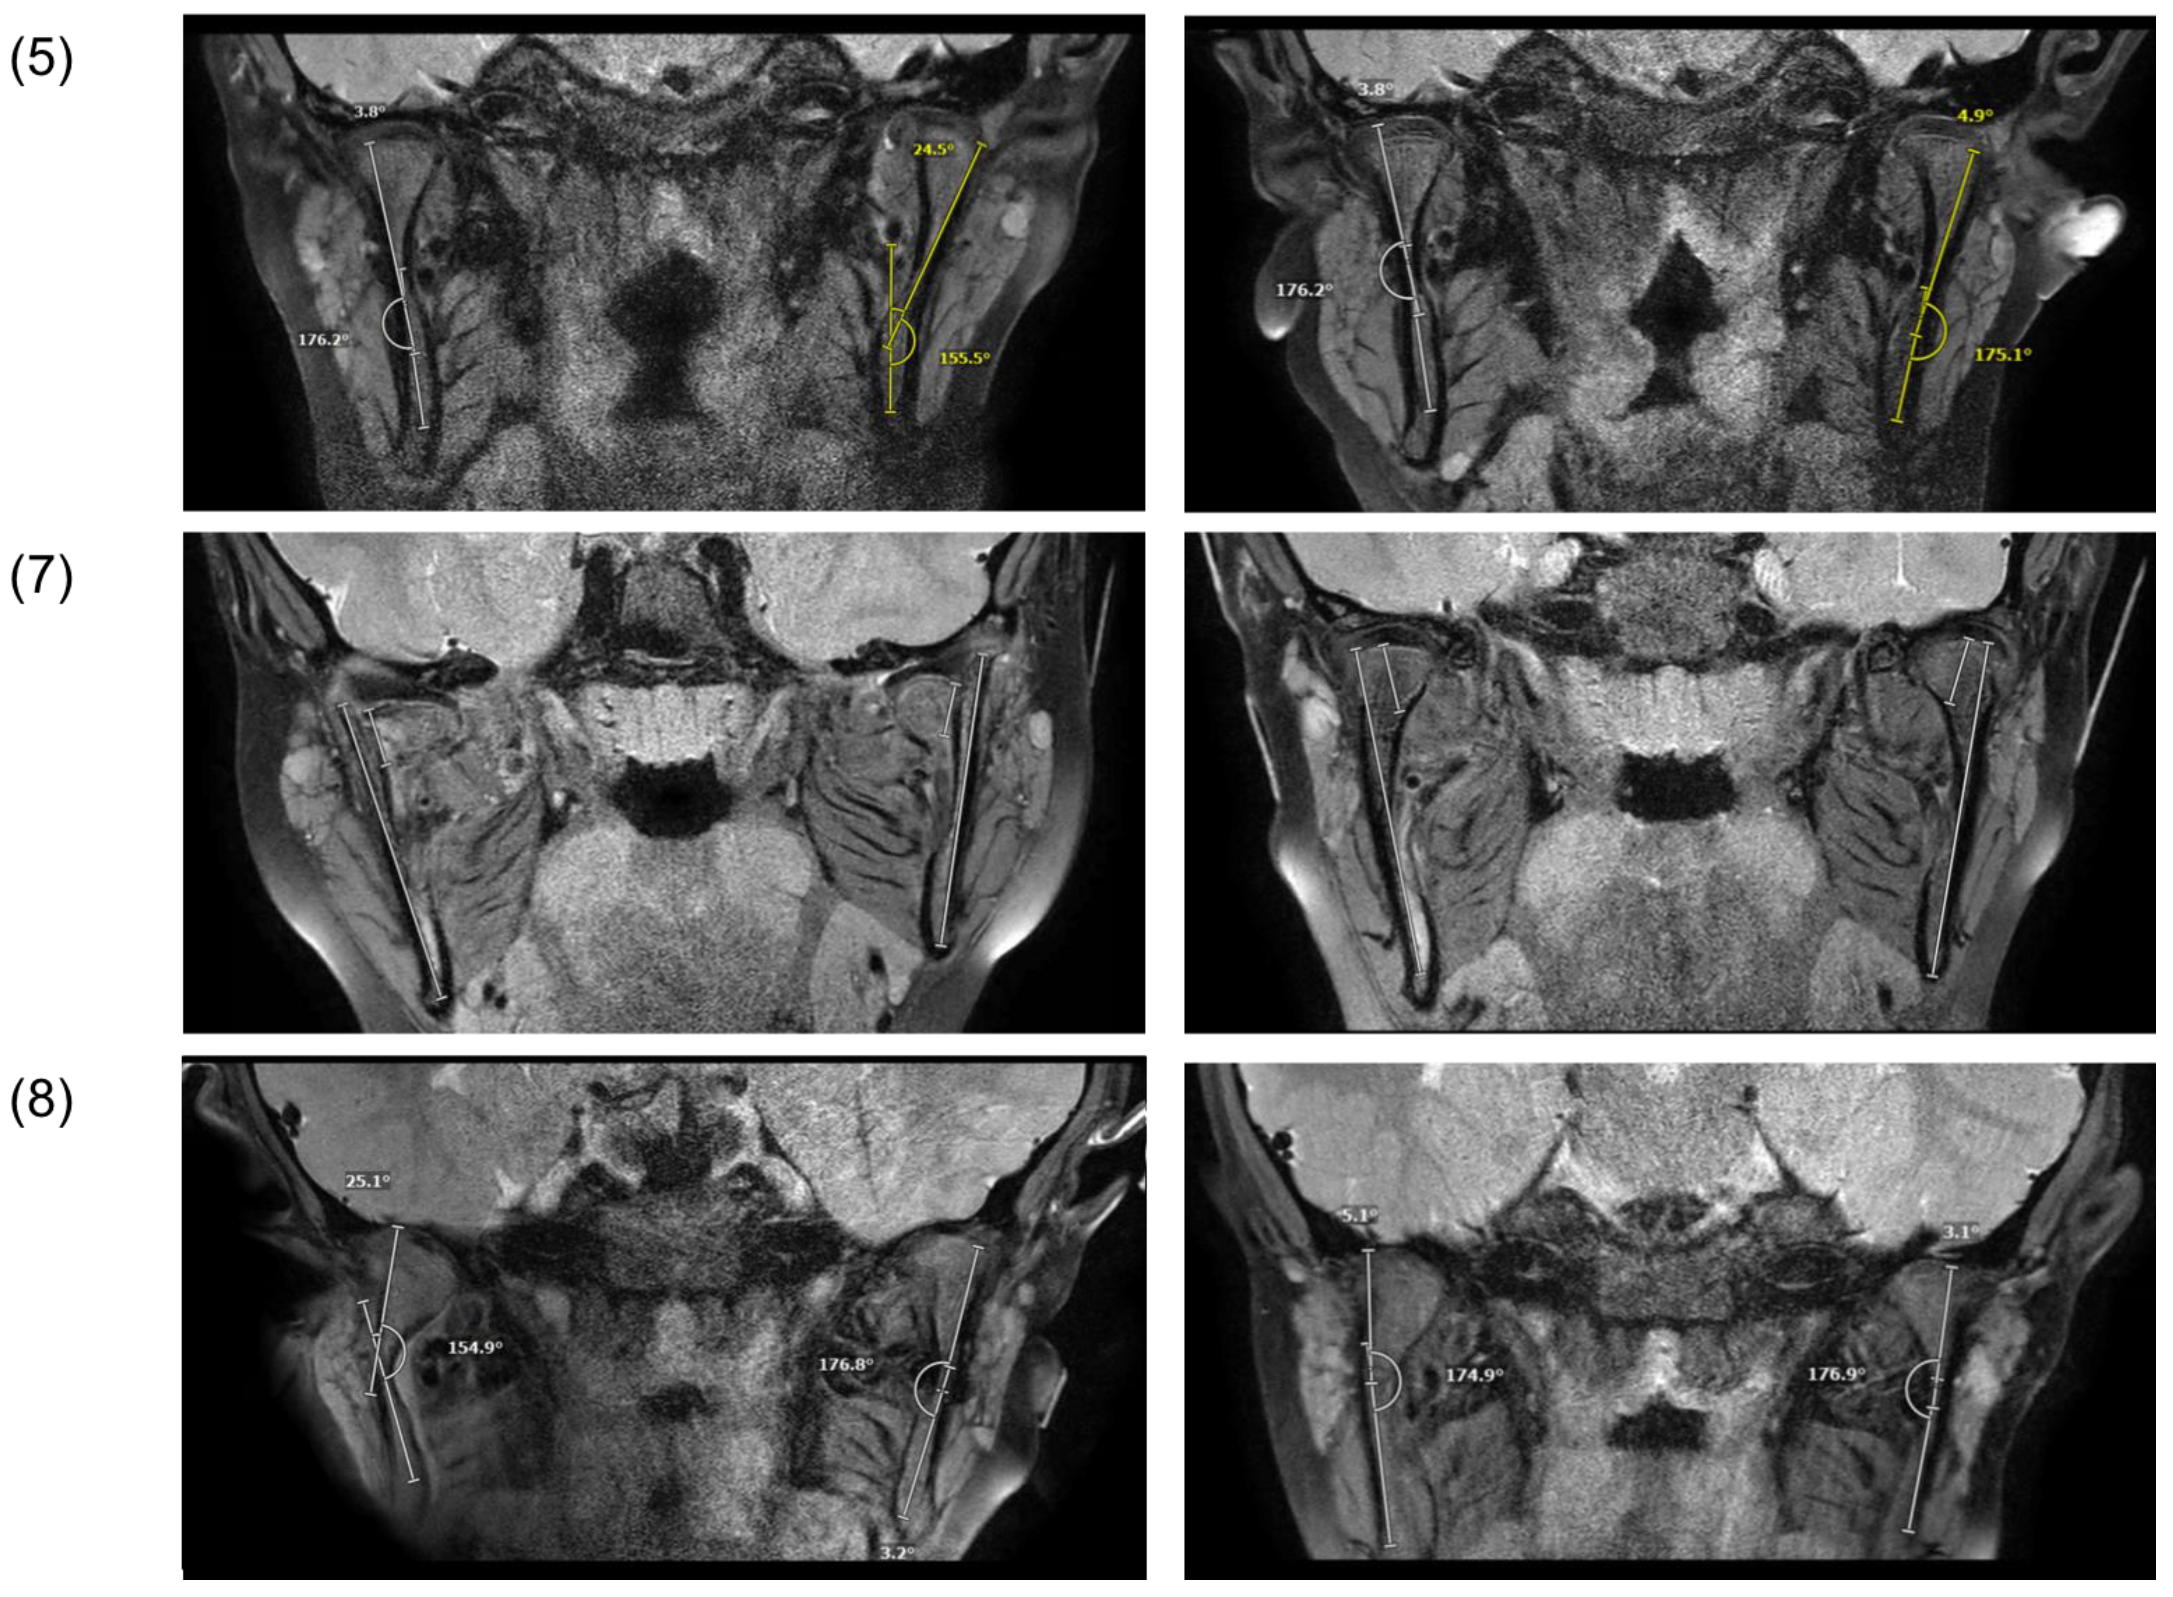

3.3. Radiological Findings

| (5) | M | 10 years, 7 months | Play | Left | Subcondylar fracture | - | 0 | - | 1 | 1, l | 1 | 0 | 0 | 1 | 25° | 4.5 mm |

| (7) | M | 8 years, 6 months | Bicycle | Bilateral | Right: condylar head fracture | P | 1 | 2 | - | - | 1, a | - | 1 | 1 | - | 5.5 mm |

| Left: condylar head fracture | P | 2 | 1 | - | - | 1, a, m | - | 1 | 1 | - | 9 mm | |||||

| (8) | M | 5 years, 7 months | Fall | Right | Subcondylar fracture | - | 0 | - | 1 | 1, m | 0 | 0 | 0 | 1 | 25° | 3 mm |